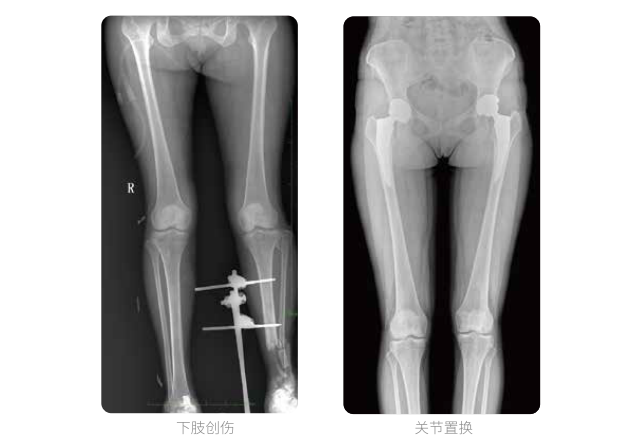

雙下肢臨床影像

髓內(nèi)釘手術(shù)是骨科、手足外科中常見的微創(chuàng)型手術(shù)方式,患者隨訪時(shí)需拍攝置入在股骨、肱骨處的較長髓內(nèi)釘。PLX8600視野拍攝,能夠出色解決醫(yī)生需多次攝影再拼接的痛點(diǎn)。一次成像雙下肢,即拍即得,高效率,無需拼接。工作站軟件自帶的測量功能方便醫(yī)生讀取雙下肢長度數(shù)據(jù),助力準(zhǔn)確診斷。

動(dòng)態(tài)DR所具備的全脊柱、全下肢全景成像技術(shù)檢查,能夠更加清晰的顯示患者病情變化情況,對骨科疾病患者的全脊柱、全下肢病變情況圖像展示更加具有完整性,對患者在自然狀態(tài)下的應(yīng)力情況展示較為全面,有助于骨科疾病患者臨床診斷效果的提升,對患者臨床治療方案的科學(xué)制定有著積極的作用。